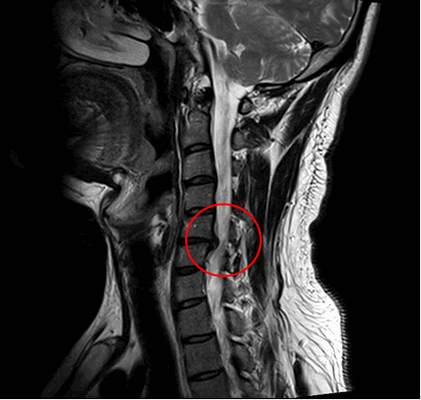

Ущемление позвоночного канала вледствие выпячивания диска.

В противном случае заболевание примет агрессивный характер, что приведет к сильному сужению спинального канала, защемлению нервных корешков и/или пережиму артерий, возможно, к поражению спинного мозга со всеми вытекающими последствиями. Тяжелые состояния лечатся исключительно хирургическим путем.